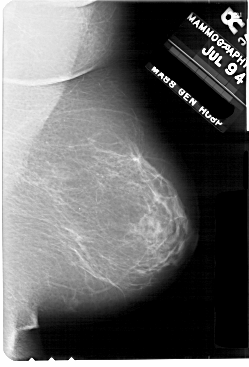

A_1707_1.RIGHT_MLO

RIGHT_MLO LINES 5491 PIXELS_PER_LINE 3721 BITS_PER_PIXEL 12 RESOLUTION 43.5 NON_OVERLAY